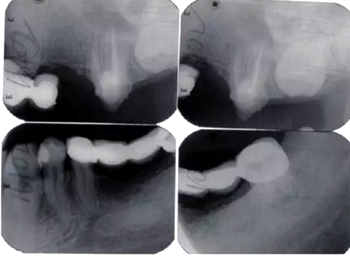

全口根尖X線片示鄰面骨嵴頂影像模糊;根管欠填、根充不致密,、未見根管治療影像,、根尖周可見低密度影像(圖2)。

圖2 患者初診時(shí)全口根尖X線片